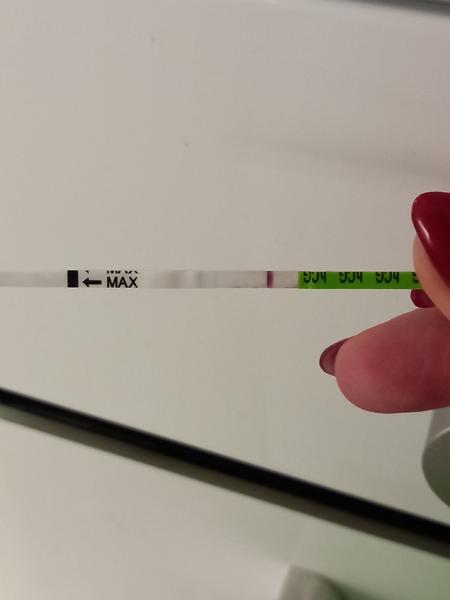

Duch na teste

ahojte babule, mam taku otazku...mate skusenost ze pocas 3 dni vam nesilnela druha ciarka na teste ale bola rovnaka???ako duch????

@zuzsat baby uvidíme na sono ideme týždeň tak uvidíme. Len určite aj trvalo tomu vajíčku sa vôbec spojiť čiže reálne to mohlo byt až v nedeľu večer niekedy, a ja som testovala minulý pondelok a tam nebolo nič ani duch na 9dpo, prvý duch bol až v piatok, čo bolo 13dpo a to vtedy ukázal aj digi test poobede. Tak ja stále nestrácam nadej do utorka 😊je vidieť že tie testy sú raz tak silnejšie po tých 2dnoch, a možno už aj ten digi by ukázal 2-3t, v piatok bolo 1-2 neviem nemám doma iný test okrem týchto z dm

@zuzanaa2010 si zlata ale nechce sa mi verit .. kym nie je poriadne vidiet stale budem na pochybach

@esmee3 je to individuálne, mne pri prvom silnela oveľa pomalšie ako pri druhom 😎 nestresuj sa zbytočne testami. Niekto už á ducha 9 DPO a niekto až 13 DPO 😉